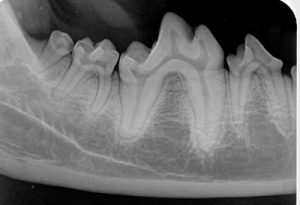

Veteriner diş hekimliği söz konusu olduğunda dental radyografi olmaksızın çalışmak kelimenin

tam anlamıyla imkansızdır. Dental görüntüleme sistemleri, diş hekimliği pratiğindeki en hayati ekipmandır. Dental radyografiler, kesin teşhis koyabilmek için gereklidir. Özellikle genç hastalarda dental radyografiler sayesinde malpozisyon durumu, anormal dişler, eksik, ölü ve canlı dişler gözlemlenebilir. Diagnoz, prognozu anlamanın temelini oluşturur ve hastalarımızı nasıl tedavi edeceğimizin kararını vermemizi sağlar.

Evcil hayvanların diş temizliği işlemleri sırasında, kapsamlı bir ağız sağlığı değerlendirmesi ve gerekli olan tedavi yapılır. Dental x-rayler ve periodontal prob ile ölçüm değerlendirmeye yardımcı olur. Röntgen çekilmeden hastayı anesteziye alıp dişlerini temizlediğimizde önemli bir problemi gözden kaçırmış olabiliriz ve yaptığımız uygulama hastanın diş sağlığı için yeterli olmayabilir. Eğer sadece bakar(fiziksel muayene), gerçekten göremezseniz (röntgen çekmezseniz) dikkat edilmesi gereken bir problemi gözden kaçırmanız çok muhtemeldir. X-ray görüntüsü, ağız içindeki bir çok alanın değerlendirilmesine imkan sağlar

Bir evcil hayvan düşünün ki sürekli yüzünü sürtüyor, yutkunuyor veya aşırı derecede salivasyonu var ve bunların hiçbiri için ortada bir sebep yok. Tedavi edilmeden bu belirtilerin geçmesini mı beklersiniz? Yoksa teşhis olmadan tedaviye mi başlarsınız? Antibiyotik veya steriod tedavisi uzun vadede nadiren fayda sağlayan uygulamalardır, hatta evcil hayvan için zararlı olabilir. Bilinmelidir ki; hayvanlar ve insanlar için gelişigüzel antibiyotik kullanımı ilerleyen zamanlarda bakteri direncine sebep olabilmektedir. Dental radyografiler ile dişler arasında veya gingival sulkusta sıkışan yabancı cisimleri tespit edebiliriz. Böyle bir durumda sadece medikasyon ile çözüm aramak doğru olmayacaktır, en mantıklı tedavi yabancı cismi uzaklaştırmaktır. Her zaman için önce teşhis konulmalıdır, ardından en iyi tedavi planlanmalı ve gereken tedavi titizlikle uygulanmalıdır. Dental radyoloji teşhisteki “tahmin”i ortadan kaldırır ve doğru tedavinin optimal bir şekilde uygulanmasına olanak sağlar. Yukarıda görülen örnek vakalardan anlaşılacağı üzere veteriner diş pratiğinde radyografi büyük önem arz eder. Günümüzde gelişen teknoloji ile birçok veteriner hekim kliniğinde dijital radyoloji sistemleri ile çalışarak çok daha net görüntüler elde ederler. Bu sayede teşhise daha rahat ve hızlı bir şekilde ulaşarak hayvanlarımızın sağlıklı bir yaşam sürmelerini sağlar.